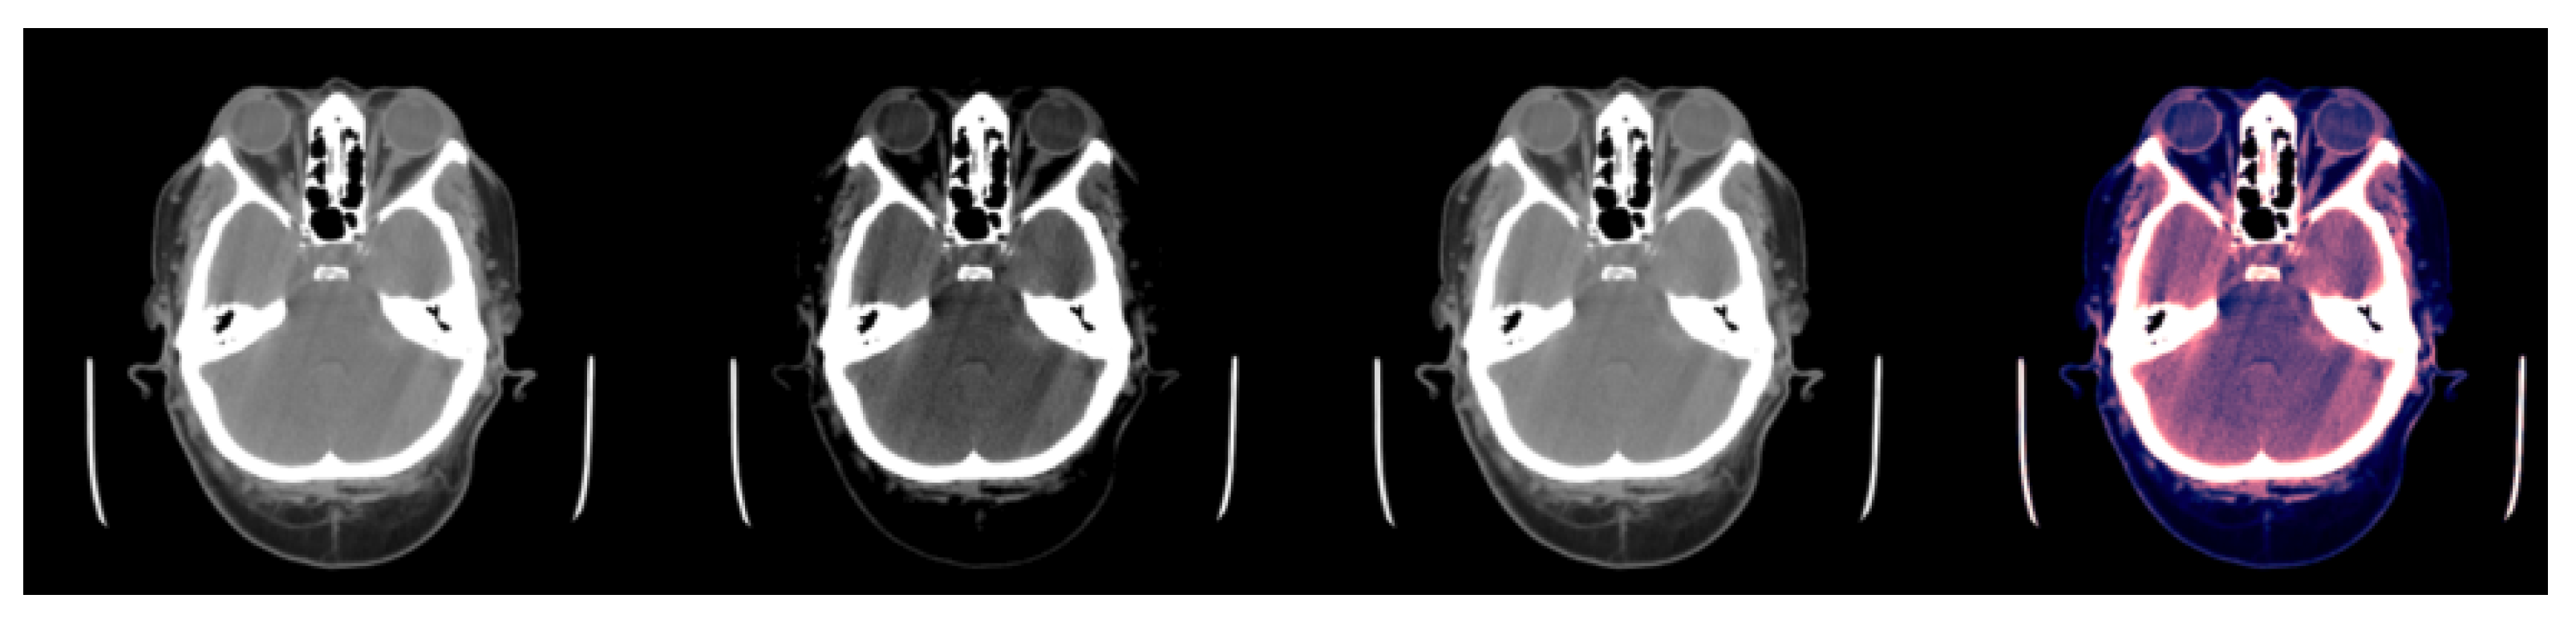

Figure 1 and Figure 2a illustrate the use of our model. An image where the model predicts bleeding (ICH) with a probability of 0.9897 is shown, and, in addition, Grad-CAM was able to determine the bleeding area to make that decision. Appendix A.2 provides a more technical description of this technique.

Figure 1.

Example of slice windowing as pre-processing of an HU matrix to obtain three different matrices (window used between brackets). From left to right: (1) slice with [0.80], (2) slice with [−20, 180], (3) slice with [−150, 230], (4) the three windowed slices stacked (each channel is associated to one color RGB for visualization purposes).

As our neural network took three channels (i.e., a RGB image) as input, the scans with the HU matrices had to be pre-processed to obtain three matrices of size pixels, one for each channel. To obtain these three matrices, three different windows were applied to every slice. Applying a window with X as lower bound and Y as upper bound meant that all HU values lower than X were converted to X, all HU values greater than Y were converted to Y, and the rest remained the same (see Figure 1).